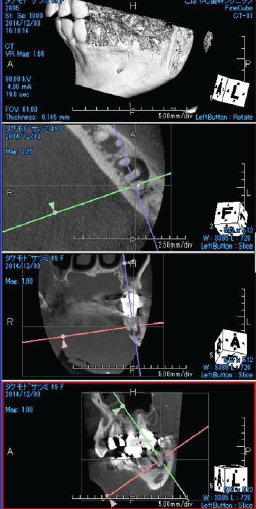

術前のレントゲン像とCBCT像(図11・12)元々根尖部が吸収し大きな根尖病変を有する症例。

CBCTでは唇側皮質骨が広範囲に渡って吸収している。歯根が短く歯冠:歯根比が悪い状態。

外科的歯内療法のアプローチも考えられるが、歯冠:歯根比を考慮し非外科的歯内療法のアプローチを選択。根尖部のゲージングは#100を示した。作業長1ミリアンダーに抵抗形態を付与し、根管充填材が根尖外に漏出することを避ける。MTAセメント(PRO ROOT ®️)にて根管充填を行う(図13)。

術後5年経過、根尖周囲の透過像も軽減し、CBCT像では喪失していた唇側の皮質骨の再生が認められる(図14・15)。

(図11)右上1番は歯髄描壊疸

左上1番大きな骨欠損を伴う慢性根尖性歯周組織炎を呈する

(図12)左上1番の根尖部付近の骨はCBCT上で

唇側皮質根も含め大きく欠損していることが確認できる